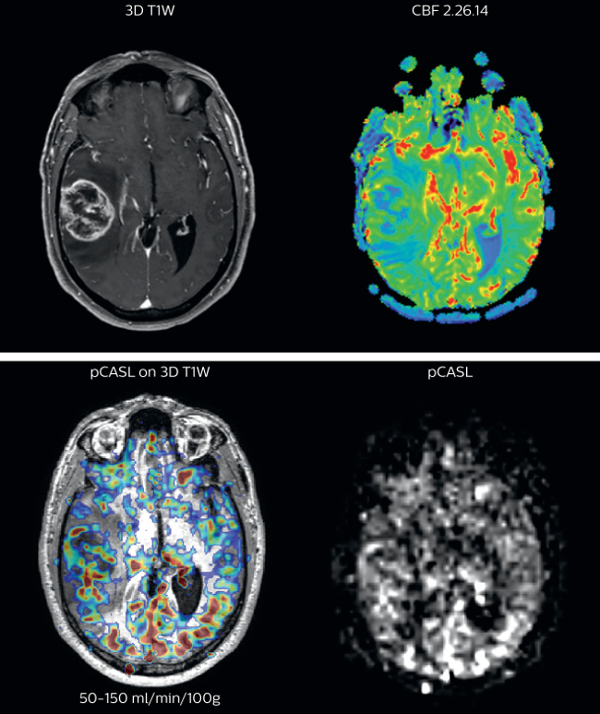

Cerebral blood flow in glioblastoma

The pCASL perfusion map overlaid on the 3D T1 image demonstrates a peripheral rim of elevated cerebral blood flow corresponding to the centrally necrotic glioblastoma.

The pCASL-generated CBF closely approximates the rim of elevated rCBV obtained with DSC contrast-enhanced perfusion imaging.

Scanned on Achieva 3.0T dStream

“We have compared pCASL to T2*-weighted perfusion imaging with contrast agent in patientswith brain tumors”, says Dr. Nickerson. “In the cases included in our study, pCASL was at least as representative as perfusion with contrast agent. It’s a pretty big improvement if we’re avoiding giving gadolinium and we’re getting a quite equivalent dataset, that’s a pretty big improvement.”